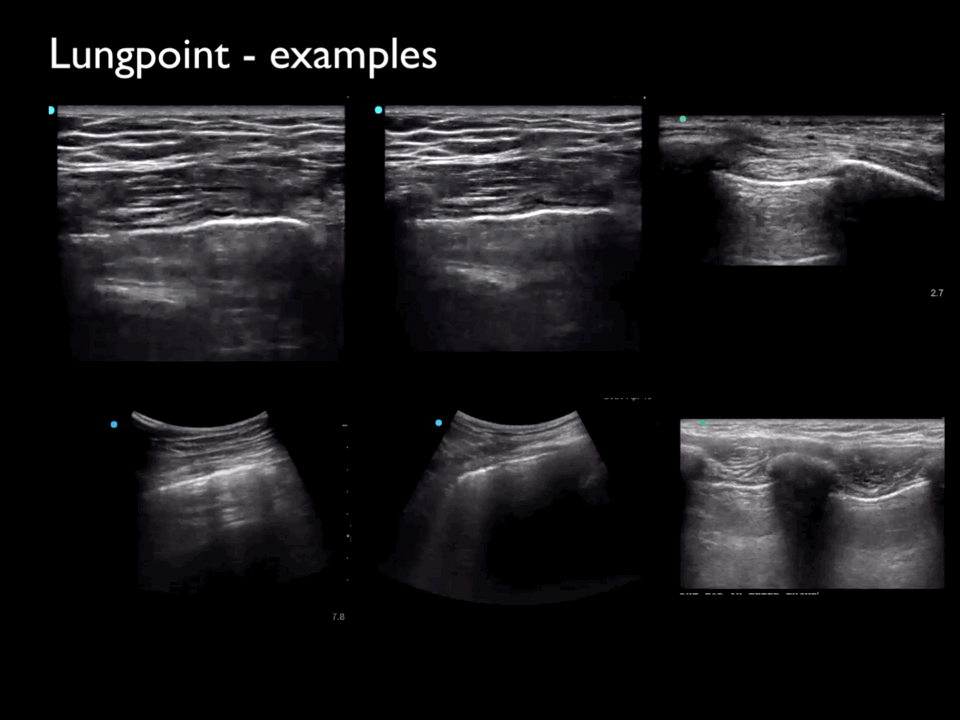

Six ultrasound clips, each demonstrating the “lung point” in different patients with pneumothorax, showing the transition between the non-sliding area of the pneumothorax and the normal sliding lung.